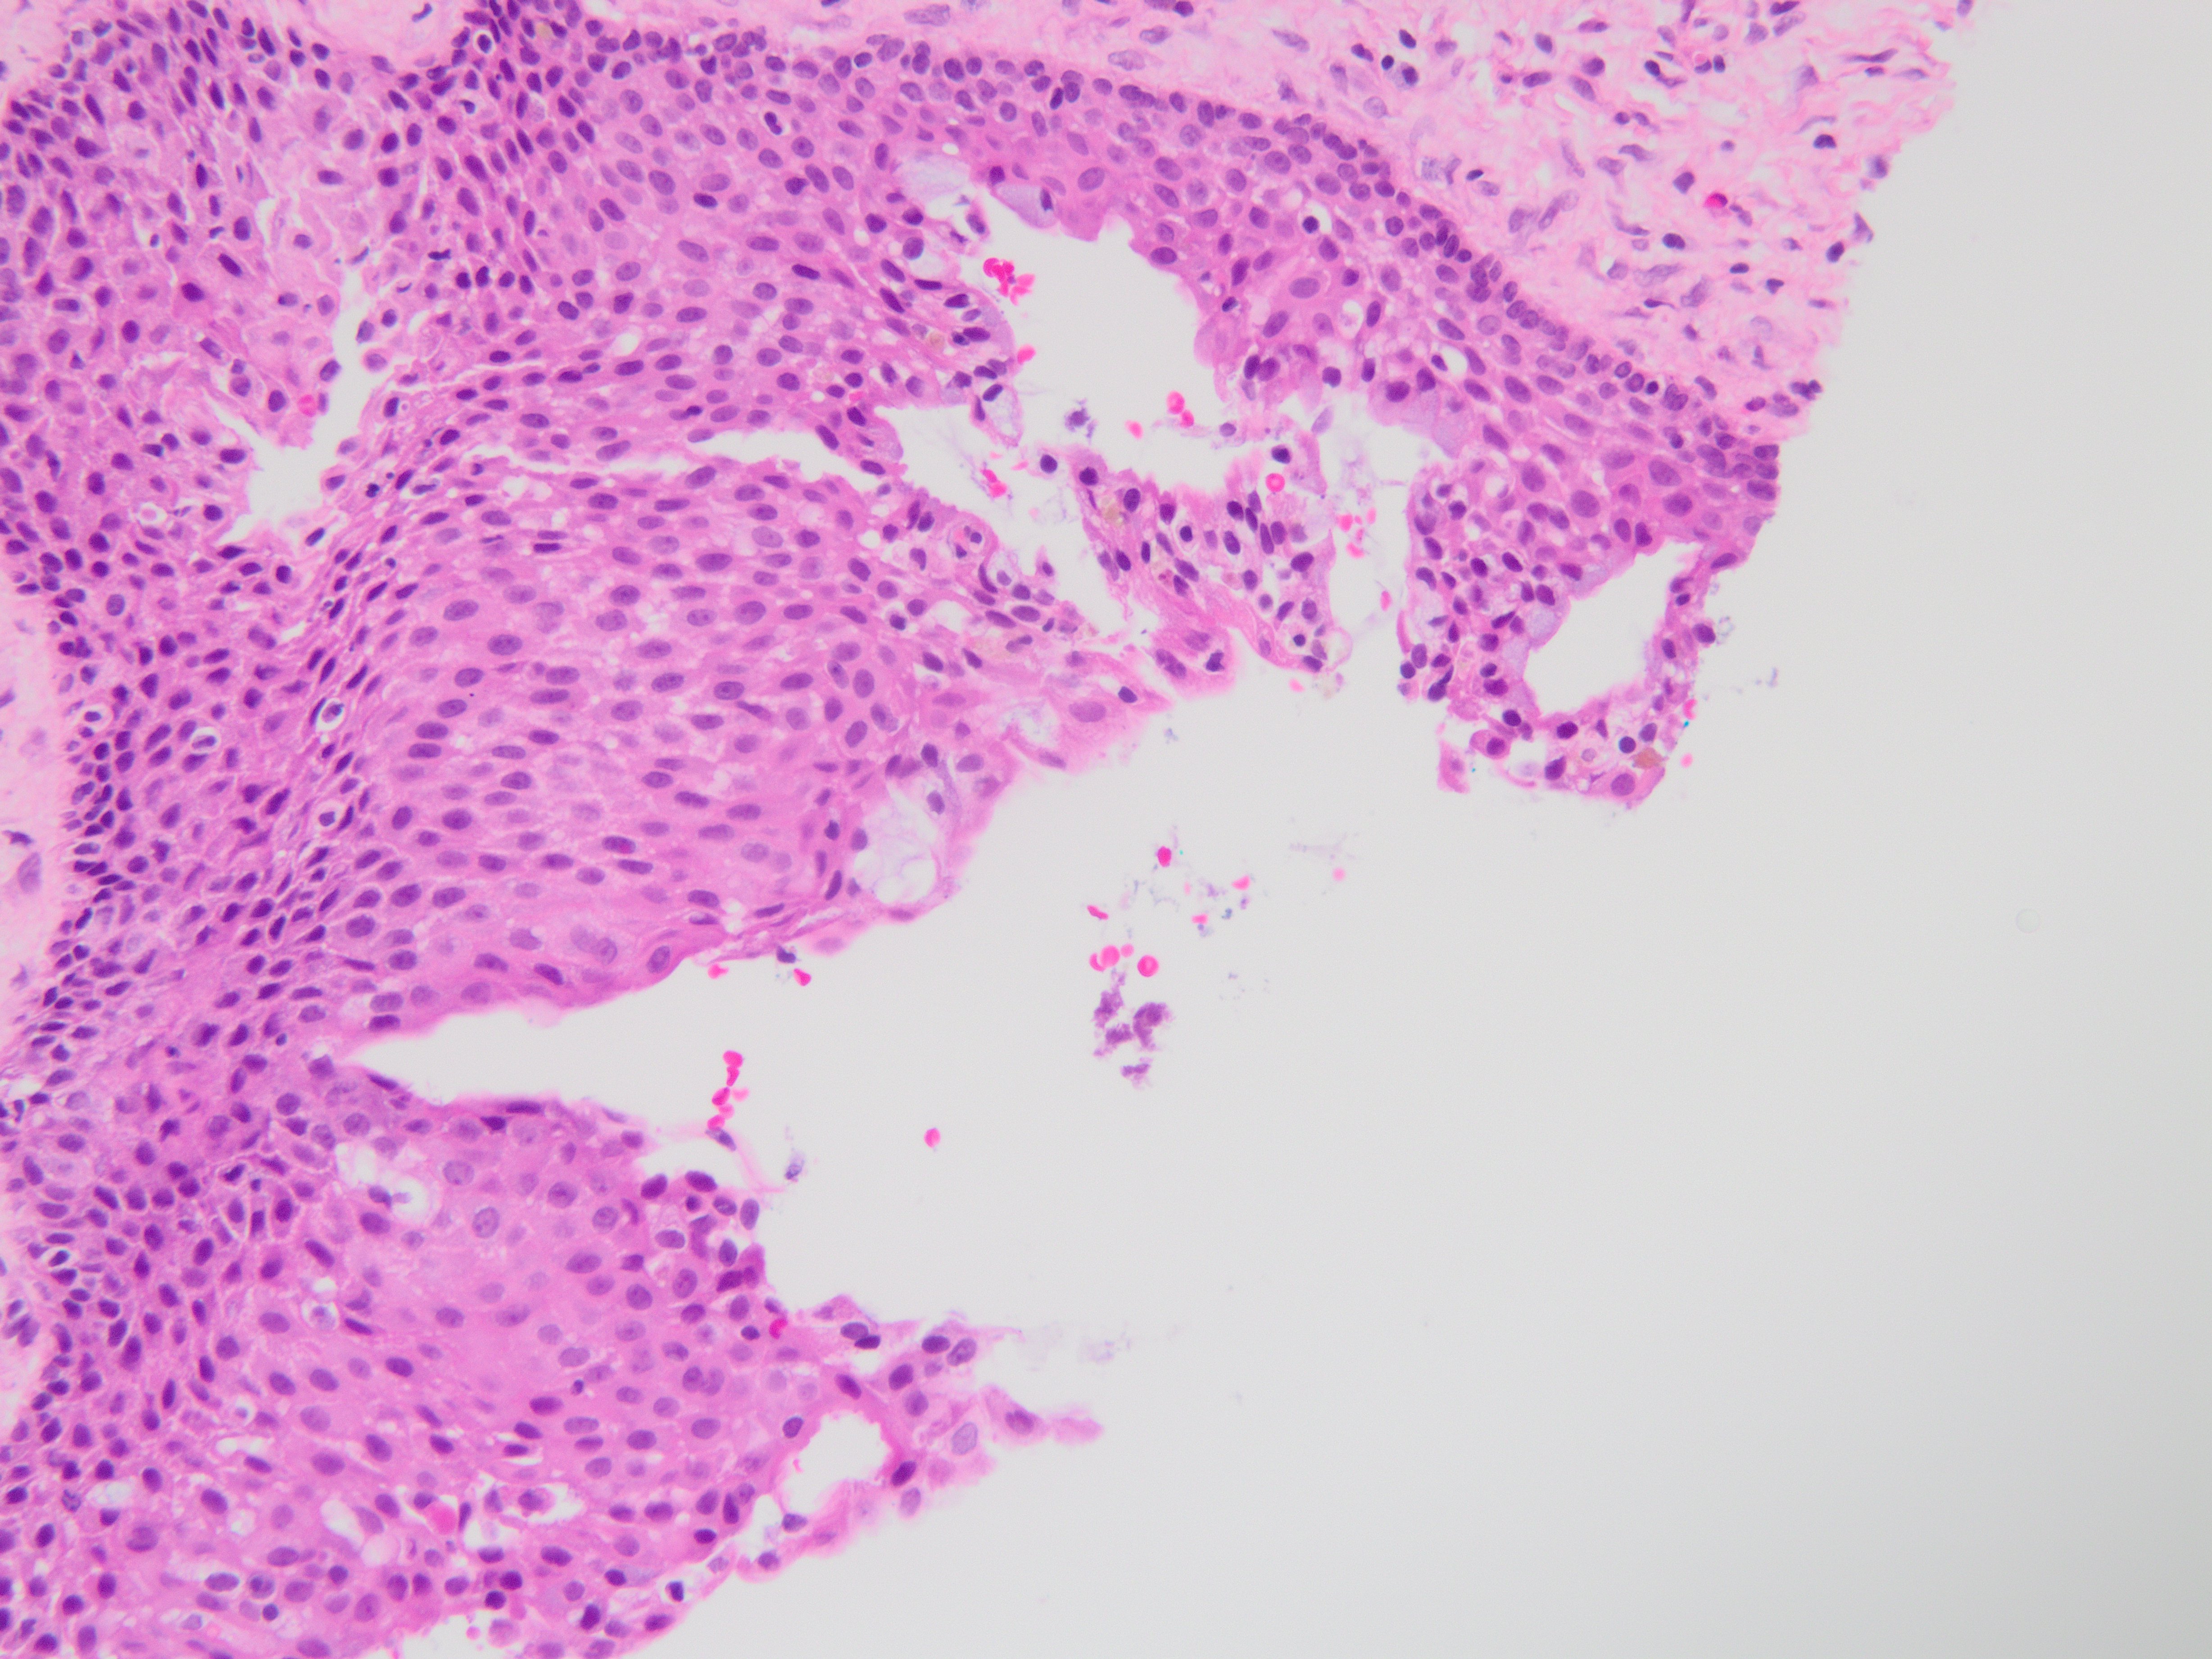

Brief explanation of the answer: Sections show cyst lining of variable thickness with mucous cells, ciliated cells, eosinophilic cuboidal cells, and clear cells. There are multiple compartments. Microcysts, papillary projections and epithelial spheres are present. These features are consistent with glandular odontogenic cyst. Resection is recommended due to high recurrence rate.

No basal cell palisading or parakeratin is noted, excluding odontogenic keratocyst. Periapical and radicular cysts tend to have a squamous lining with abundant inflammation. Mucoepidermoid carcimoma tends to be more proliferative with invasive features, and also shows intermediate and epidermoid cells.